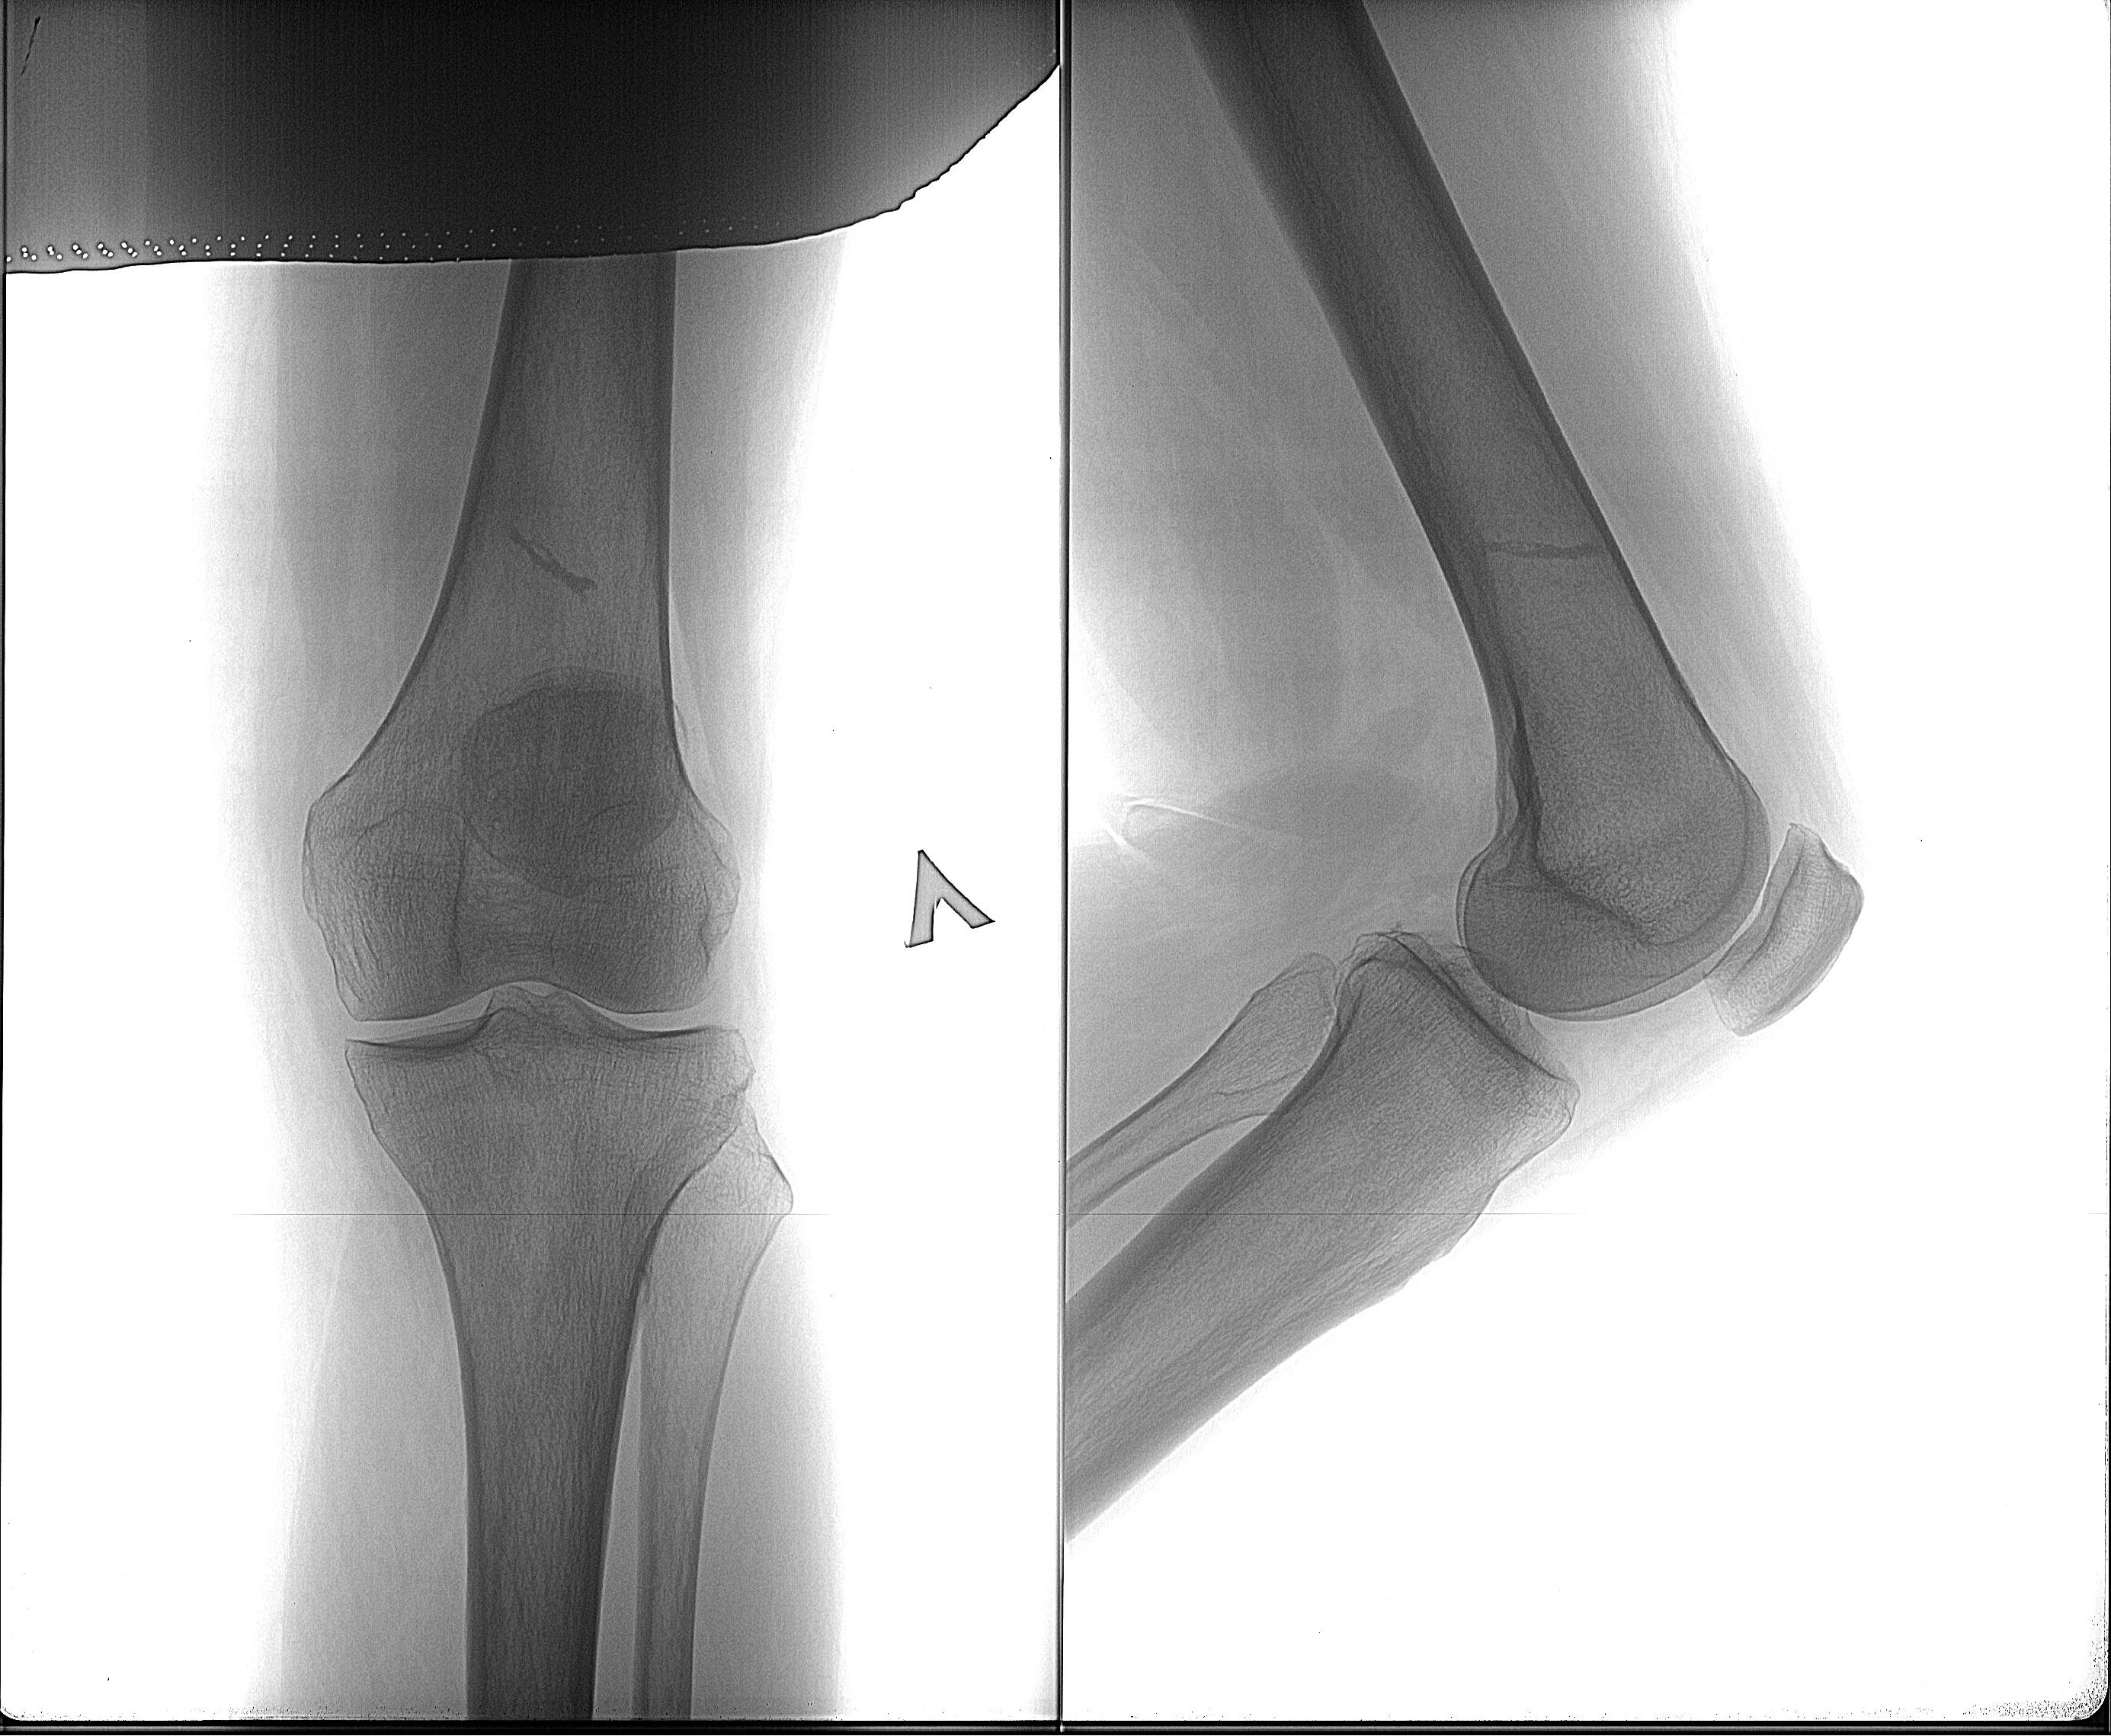

Рекурвация коленного сустава: рентгеновские снимки и объяснения